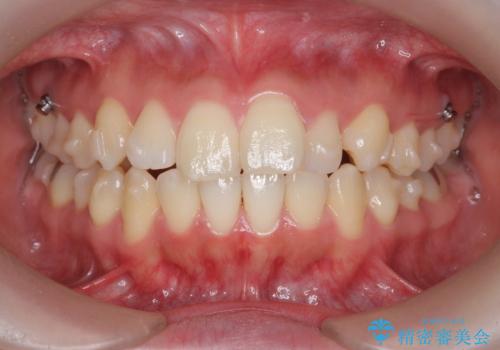

- 前歯の角度の改善を求めて矯正治療を希望し来院されました。

上下の歯は、上顎の歯が相対的に前に位置する咬合関係で押し出されるように前歯に角度がついている状態です。

咬合関係の改善、前歯の角度、がたつきを改善するため、マイクロインプラントを用いて上顎の奥歯を後方へ移動させていきます。